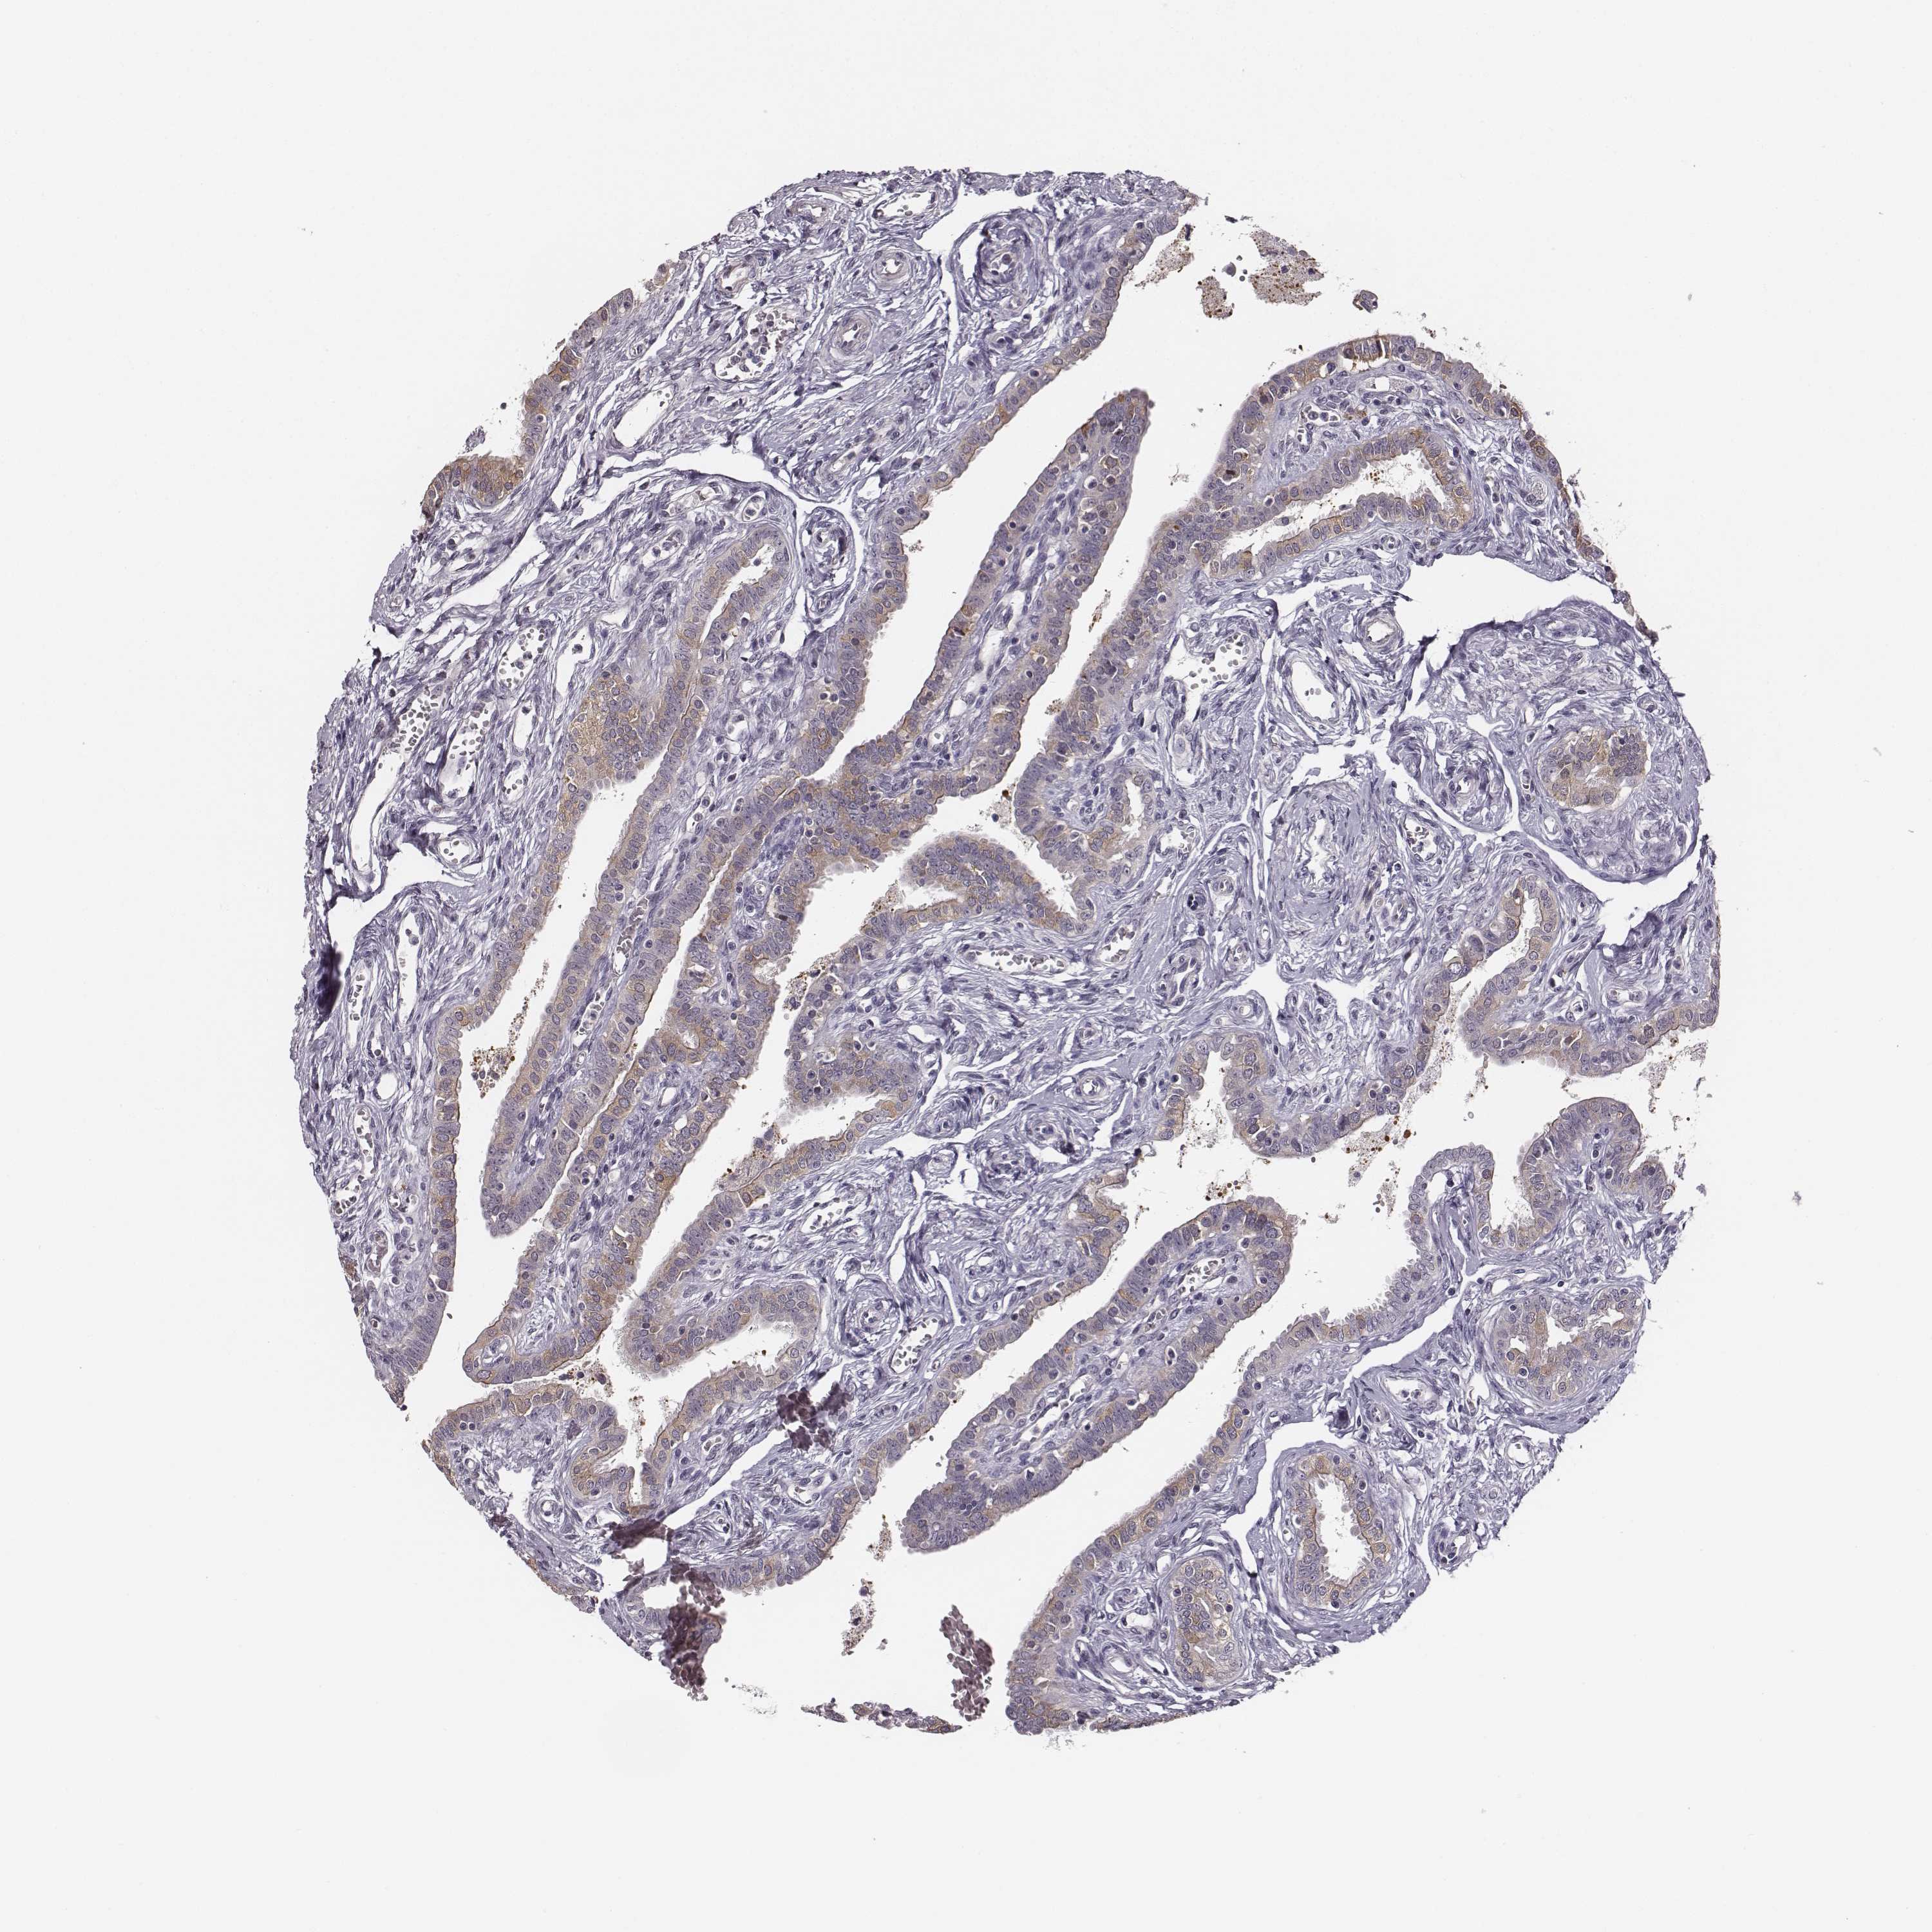

KAAG1